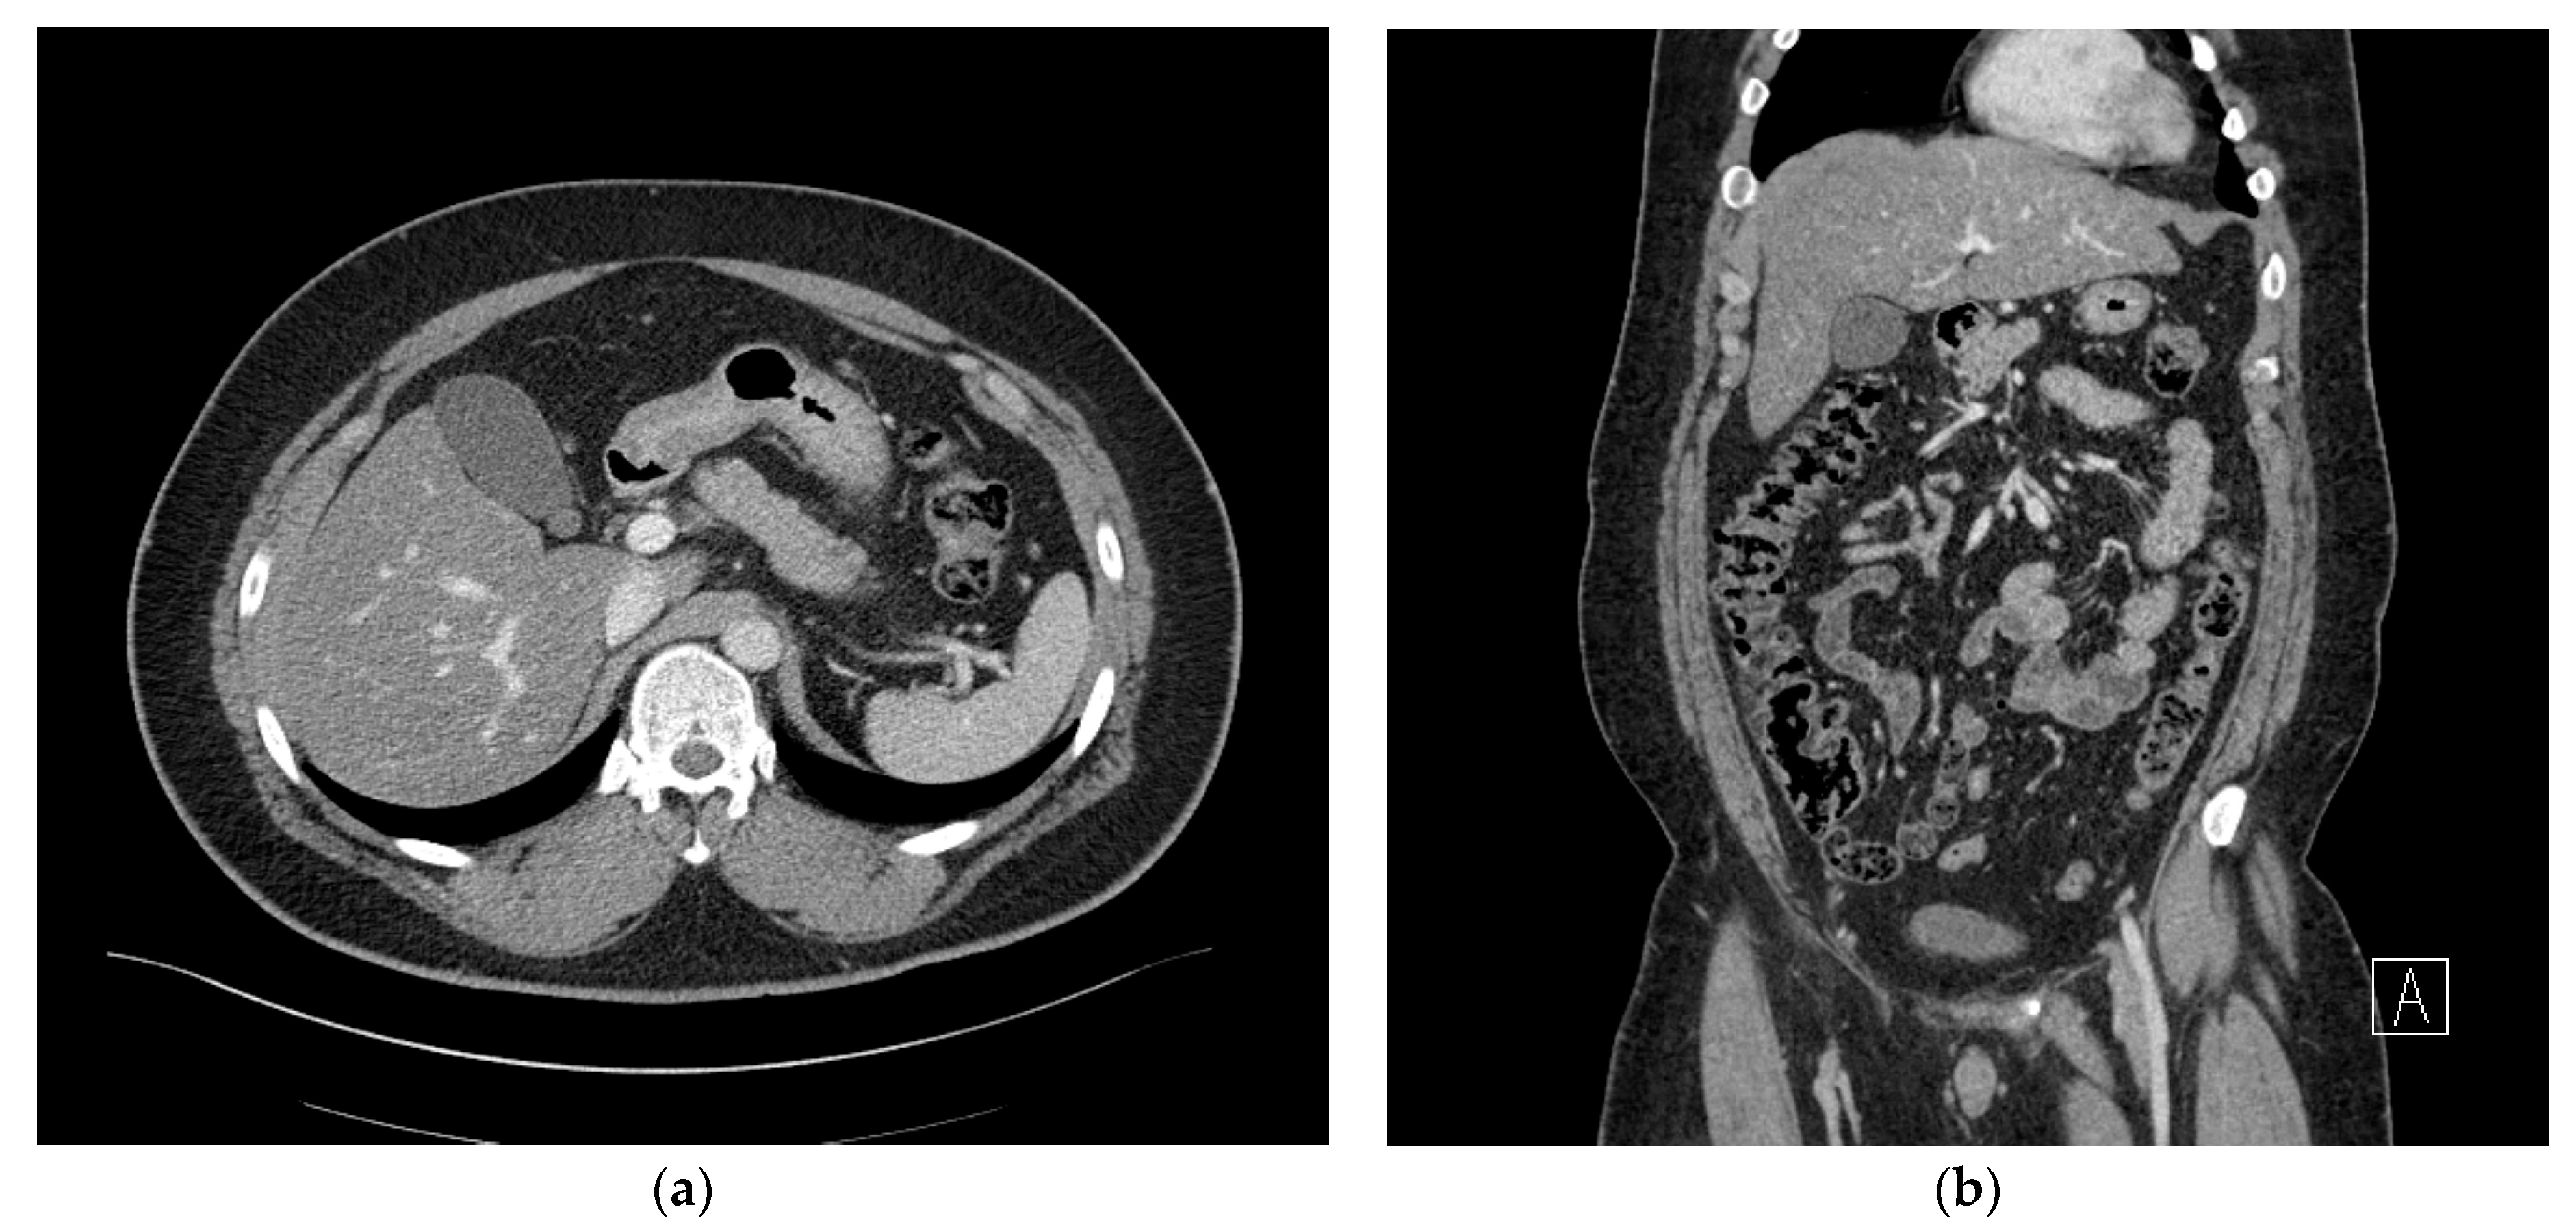

The abscess was effectively drained, and the right upper abdominal tenderness improved after 3 days (Figure 4a,b). However, a severe cough developed, and percutaneous drainage was performed for right pleural effusion. Chest CT was performed the following day as the cough did not sufficiently improve. Chest CT showed that the subhepatic abscess had markedly reduced, but the pleural effusion was multiloculated and had not been sufficiently drained. We drained the remaining pleural effusion through chest tubing.

Figure 4. (a) Axial view of the abdominal computed tomography (CT) scan showing the multiloculated fluid collection in the subhepatic space showing significant improvement. (b) Coronal view of abdominal computed tomography (CT) scan demonstrating improvement in the adjacent transverse colon wall thickening, which was associated with inflammatory changes.